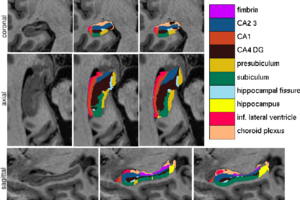

Figure 1 compares the manual and automated segmentation results qualitatively on a set of cross-sectional slices. The upper half of figure 2 shows the average Dice overlap measure for each of the structures of interest, along with the minimum and maximum across the 5 subjects. The lower half of the figure shows, for each structure, the volume differences between the automated and manual segmentations relative to their mean volumes. An example of our mesh-based probabilistic atlas, derived from 4 manually labeled hippocampi, is shown in figure 3.

Fig 1. From left to right: ultra-high resolution MRI data, manual delineations, and corresponding automated segmentations.